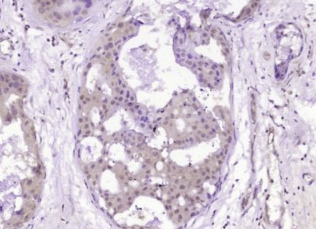

多聚甲醛固定,石蜡包埋(人乳腺癌);经柠檬酸钠缓冲液(pH6.0)煮沸15min后获得抗原;用3%过氧化氢阻断内源性过氧化物酶20分钟;阻断缓冲液(正常山羊血清)37℃30min;用α-肌动蛋白4负荷控制抗体多克隆抗体Unco孵育在4°C温度下,1:400整晚注射,然后根据SP试剂盒(兔子)说明和DAB染色进行操作。